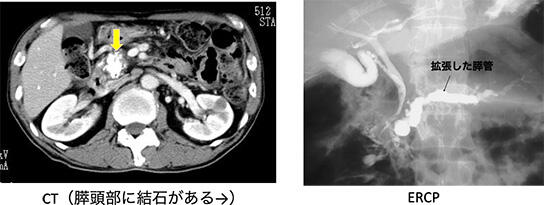

初期には、多くの場合では強い腹痛発作を繰り返します。進行すると消化吸収不良による下痢や体重減少、糖尿病が出現します。場合によっては、膵臓に石ができたり、膵管(膵液の通り道)が、太くいびつになったりすることがあります(図2)。このような状態になった慢性膵炎は元には戻らない(不可逆性)と考えられます。慢性膵炎になると膵癌の発症リスクが7 ~ 11 倍に上昇し、寿命も平均より10 年ほど短くなるといわれています。

慢性膵炎は、日本膵臓学会が定めた慢性膵炎臨床診断基準により診断します。(表) 腹部超音波検査やCT検査により、膵臓の中に膵石があるときや、内視鏡的逆行性胆管膵管造影(ERCP)や核磁気共鳴法による胆管膵管像(MRCP)によって不規則な主膵管拡張があれば、画像だけで慢性膵炎と診断されます(図4)。しかし、このようなはっきりとした所見のある慢性膵炎では、治ることはなく進行を止めることはできません。そこで、最近では、もっと早い時期の慢性膵炎を診断して、病気の進行をくいとめようという試みとして、早期慢性膵炎という病名が提案されています。そのためには、より膵臓の細かい変化をとらえることが必要です。胃や十二指腸に挿入した内視鏡の先端の超音波装置から膵臓を観察する超音波内視鏡(EUS)により膵臓を検査して、膵臓内の細かい変化を観察して診断する試みが進行中です。